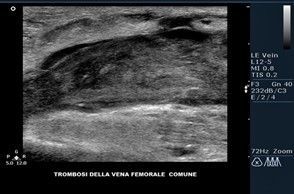

Ecocolordoppler venoso

È possibile seguire l’asse venoso, superficiale o profondo, localizzare e quantizzare l’estensione del reflusso lungo tutto il suo decorso cranio-caudale.

- presenza di ostruzioni (trombi)